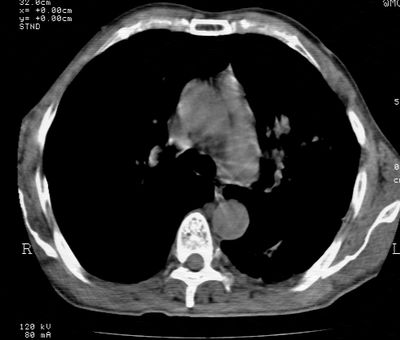

标题: CT24000:M65,胸痛,胸闷月余,既往慢支,肺气肿,肺心病 [打印本页]

标题: CT24000:M65,胸痛,胸闷月余,既往慢支,肺气肿,肺心病

左肺门肿块,相应支气管闭塞,左肺上叶、舌叶大片及散在高密度影,部分呈不张改变,两肺纹粗乱,左侧胸腔积液。考虑左侧中央型肺癌伴阻塞性改变。

左肺门见巨大软组织肿块影,直径约--,境界清,左上肺叶支气管变窄,左上肺舌叶见大片状密实影,余肺纹理增多、紊乱、纤细、部分网格状,两肺透亮度增高,纵隔内见增大多发淋巴结影,心影略左偏,左侧少量胸腔积液。

左侧中央型肺癌伴左上肺舌叶不张、纵隔淋巴结转移,左侧少量胸腔积液。